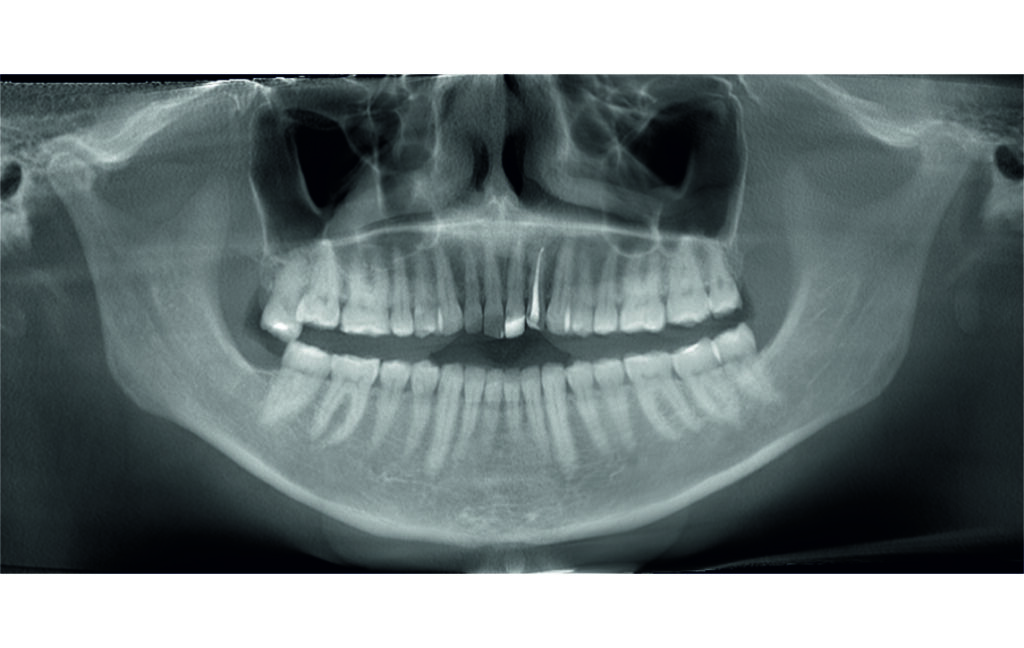

Angle Class II 2mm on the right, Angle Class II 2mm on the left, light mandibular asymmetry to the right, lower central line 1mm to the right, upper central line 1,5mm to the left, 1mm overjet and overbite. Sagittal asymmetry of upper dental arch. Light crowding upper and lower frontal segments, severe attrition of posterior teeth, night bruxism. Normal sagittal position of both jaws, high angle case, steep mandibular ramus,excessive lower facial height, open bite tendency.

The case initially presented as a moderate Class II on the right and a Class II tendency on the left, with tapered dental arches and an anterior open bite extending to tooth 26 in segment II.

In segment I, the open bite reached up to the first premolar.

A 1.5 mm deviation of the upper dental midline to the patient’s left was noted, along with a slight mandibular midline shift to the right, likely due to asymmetrical mandibular growth observed in the facial structure. Severe mesial rotations of teeth 16 and 26 were evident in the initial records. As derotation of 16, 26, 17, and 27 progressed up to aligner 16, the premolars in segments I and II moved distally, resulting in a bilateral Class I relationship, as intended in the initial treatment plan.